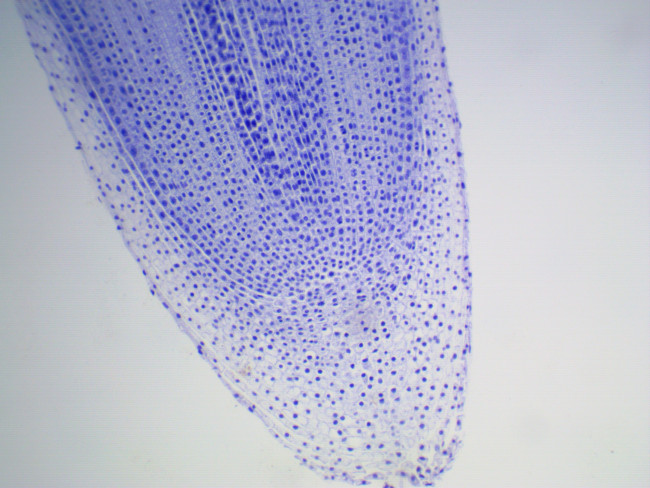

Камера ToupCam UCMOS05100KPA c сенсором Aptina MT9P006 представляет собой сенсор CMOS формата 1/2.5 дюйма, с количеством активных пикселей 2592 по горизонтали и 1944 по вертикали. Камера, благодаря однокристальной структуре, позволяет использовать оконный режим;возможности пропуска колонн и рядов и возможность получения мгновенного снимка предпросмотра (т.н. “snapshot”).

В камере используется технология обработки изображения Ultra-Fine Color Engine которая помимо использования процесса демозаики и настройки баланса белого включает в себя коррекцию “горячих пикселей” , конверсию цветового пространства, кросс-канальную коррекцию, коррекцию цветовых параметров, гамма коррекции и так далее.